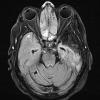

Infarct, Tract Degeneration, illustrative case (2)